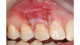

The images contained in this gallery are the property of Dr. Edward Gottesman.

Images have not been digitally altered in any way, shape, or form. These images may not be copied, downloaded or distributed without their express written permission.

Warning: Some surgical photos are intended for clinical and educational purposes and may be too graphic for some viewers.